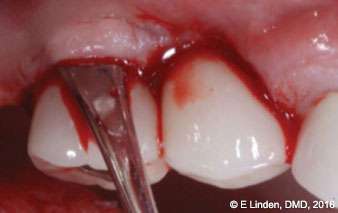

Bone sounding: Once anesthesia took effect, bone sounding was performed in order to precisely determine the bone topography (Figure 6). This step is crucial with the closed technique. The data obtained guides the clinician as to how far the laser tip needs to go into the pocket. The clinician will then move the laser tip staying 1 mm-2 mm away from the bone.

Figure 6: Preoperative bone sounding (under local anesthesia) was needed to determine the bone topography

Fiberotomy: After bone sounding was complete, the modified fiberotomy procedure was performed (Figure 8). A small elevator was used to sever gingival fibers around the affected implants in order to open up the coronal aspect of the crest of gingival tissue (2 mm-4 mm deep). This step is important as it helps to introduce the laser tip into the pocket, ensuring the most efficient delivery of the laser energy to the target tissue.